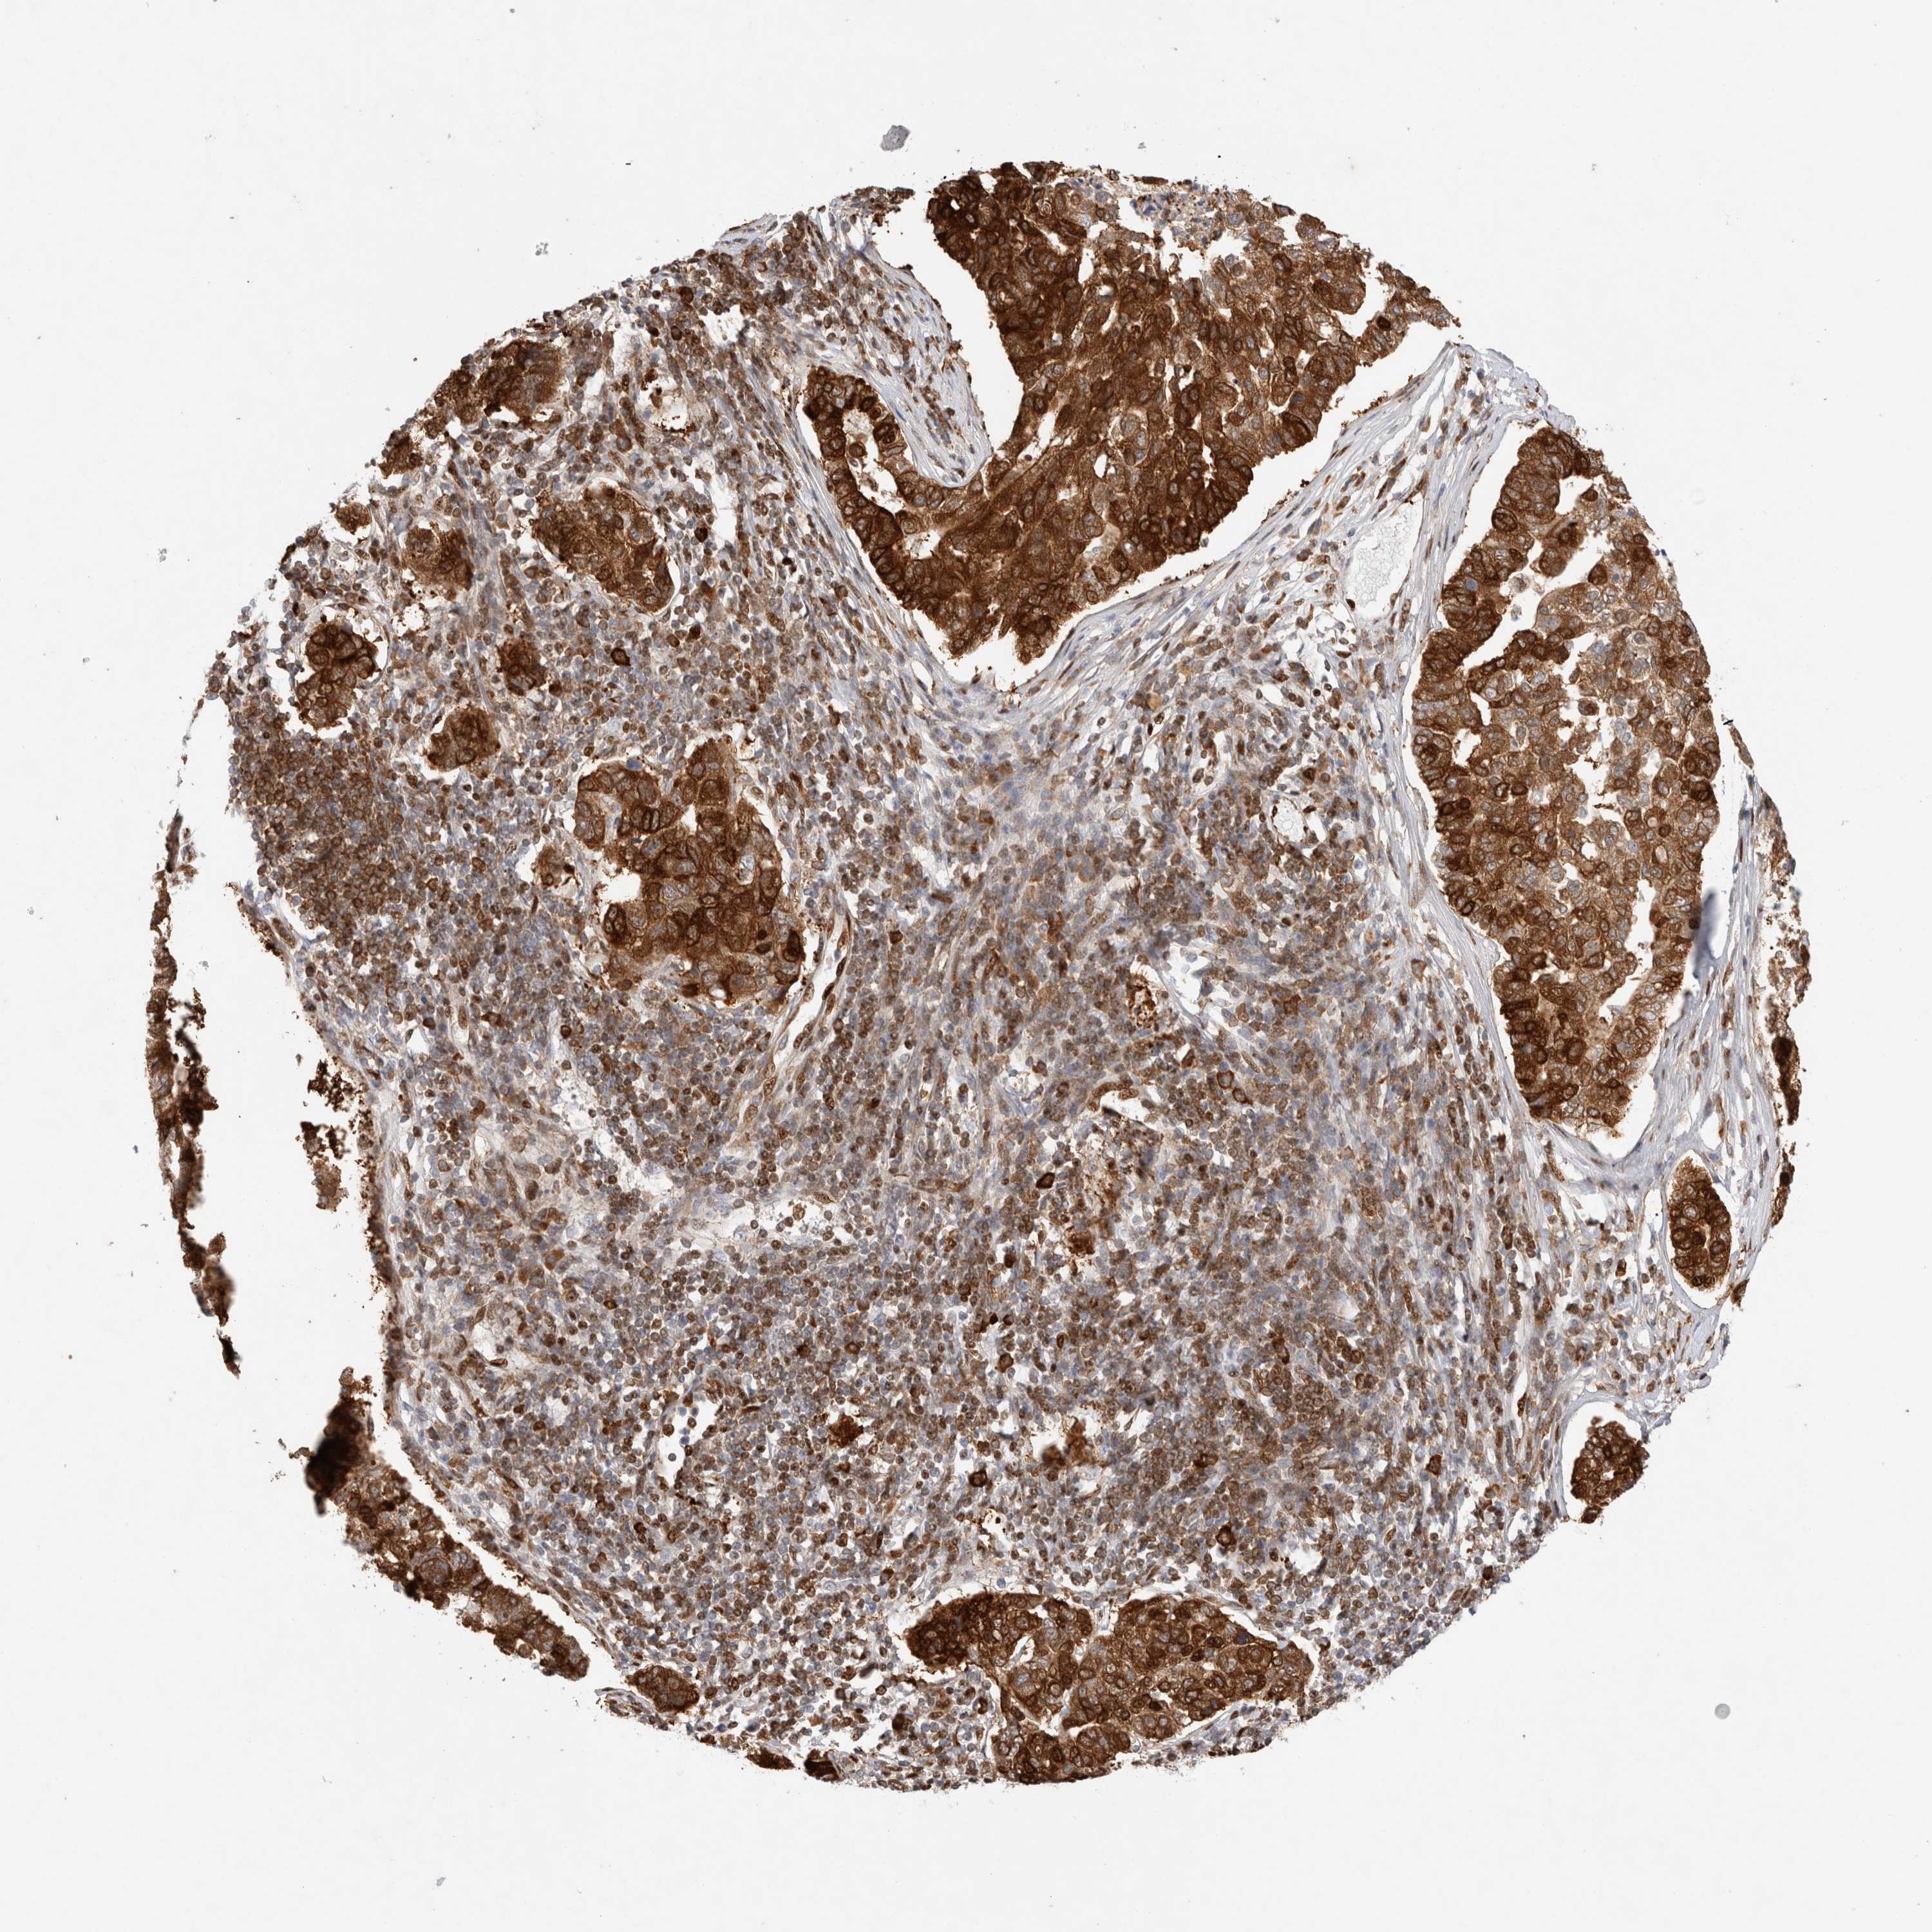

PANCREATIC CANCER - Protein expressioni

A mouse-over function shows sample information and annotation data. Click on an image to view it in a full screen mode. Samples can be filtered based on level of antibody staining by selecting one or several of the following categories: high, medium, low and not detected. The assay and annotation is described here.

Note that samples used for immunohistochemistry by the Human Protein Atlas do not correspond to samples in the TCGA dataset.

Antibody stainingi

Antibody staining in the annotated cell types in the current human tissue is reported as not detected, low, medium, or high, based on conventional immunohistochemistry profiling in selected tissues. This score is based on the combination of the staining intensity and fraction of stained cells.

Each image is clickable and will lead to virtual microscopy that enables deeper exploration of all samples and also displays staining intensity scores, fraction scores and subcellular localization as well as patient and tissue information for each sample.

Antibody HPA025958

Antibody CAB020722

Staining

High

Medium

Low

Not detected

Intensity

Strong

Moderate

Weak

Negative

Quantity

>75%

75%-25%

<25%

None

Location

Nuclear

Cytoplasmic/membranous

Cytoplasmic/membranous,nuclear

Adenocarcinoma, NOS

Adenocarcinoma, metastatic, NOS